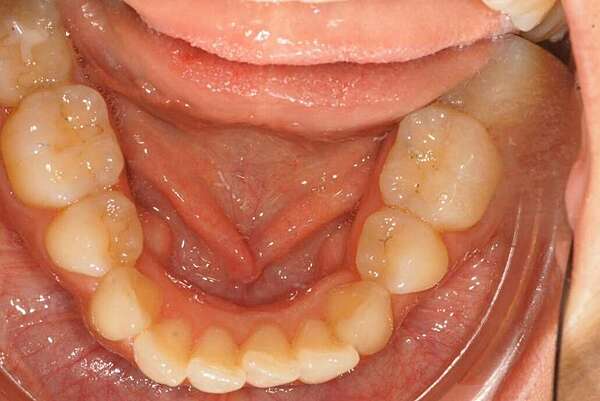

Reprise de récidive par gouttières

Reprise de traitement d'un patient ayant eu un traitement dans l'enfance